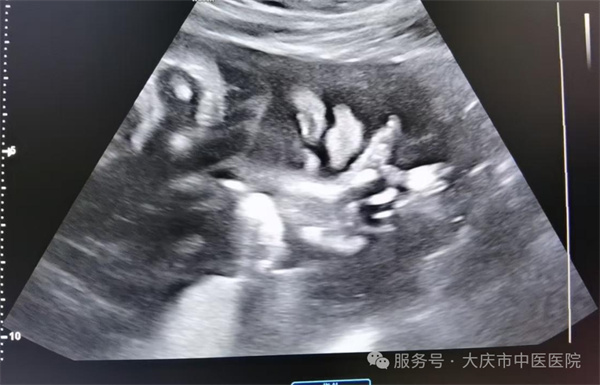

近日,大庆市中医医院超声医学科通过四维彩超筛查,为一位准妈妈做出了及时准确的胎儿发育健康提示。该孕妇为第二次妊娠,曾孕育一健康女孩,现孕23周,在超声医学科进行胎儿系统筛查时,当日值班医生,超声医学科副主任王双艳,经过一番认真细致的检查,发现胎儿存在左侧三度唇裂伴左侧牙槽突裂,其余胎儿结构未见异常。随即向孕妇及家属详细介绍唇腭裂的类型、程度及可能对胎儿出生后的影响,如影响外貌、进食、发音等,同时说明不同程度唇腭裂的治疗方法和预后情况,让孕妇对胎儿病情有全面、客观的认识。最后孕妇决定继续妊娠,足月剖产后证实了产前的诊断。截至目前超声医学科已诊断各型唇腭裂5例,均得到产后证实。

生育一个健康的宝宝是准妈妈们的最大心愿!因此四维彩超筛查十分必要。通过系统超声检查能够清晰显示胎儿颜面部的形态结构,可以实时动态观察到唇部和腭部的连续性,能直观呈现唇腭裂的部位、程度等情况,并且能清晰显示唇裂是单侧还是双侧,裂隙的大小等。让医生和家庭提前知晓胎儿情况,为是否继续妊娠等决策提供关键依据。有助于减少严重出生缺陷儿的出生,提高人口素质。 若确诊唇腭裂,医生可结合其他因素综合评估,为产妇选择更合适的分娩方式,保障分娩过程中母婴安全。诊断结果能协助临床相关科室制定出生后治疗计划,确保患儿出生后能及时得到多学科综合治疗。